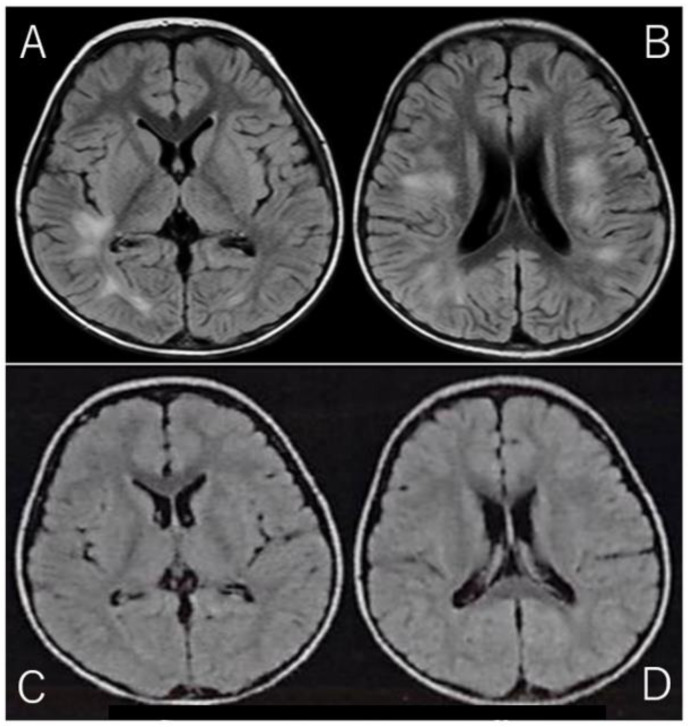

Case report: This case report describes a 3-year-old child who developed ADEM after receiving two concurrent influenza vaccines: one for seasonal influenza and one for the 2009 H1N1 pandemic. The patient presented with motor regression, mild pleocytosis in cerebrospinal fluid (CSF), and typical MRI findings of ADEM. Steroid pulse therapy resulted in rapid improvement, and the patient recovered fully without sequelae.